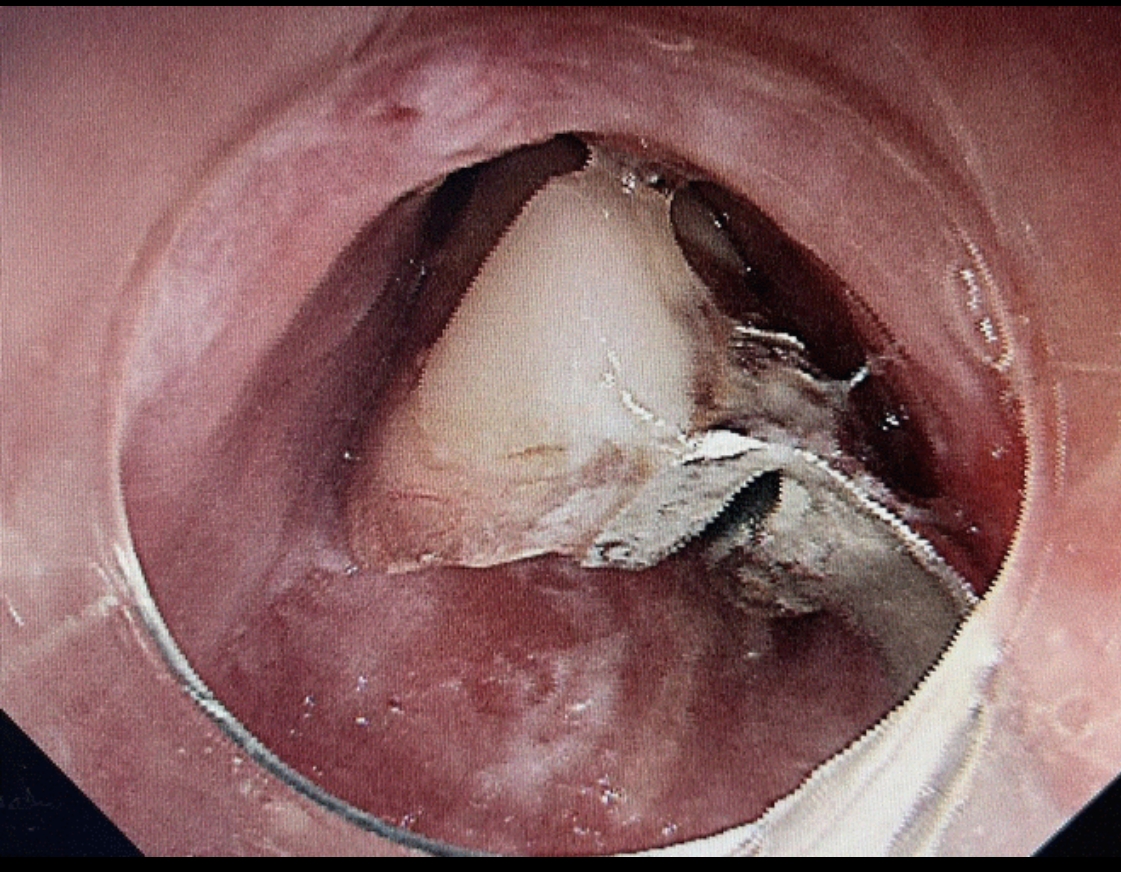

第二步:立即就醫(yī)內(nèi)鏡中心是首選??捎秒娮游哥R直觀地發(fā)現(xiàn)并取出食道的異物。

尖銳異物: 魚刺、雞骨頭、假牙等

圓形異物: 硬幣、紐扣電池、玩具零件(常見于兒童)

團(tuán)塊異物: 大塊的肉、果核、糯米團(tuán)等